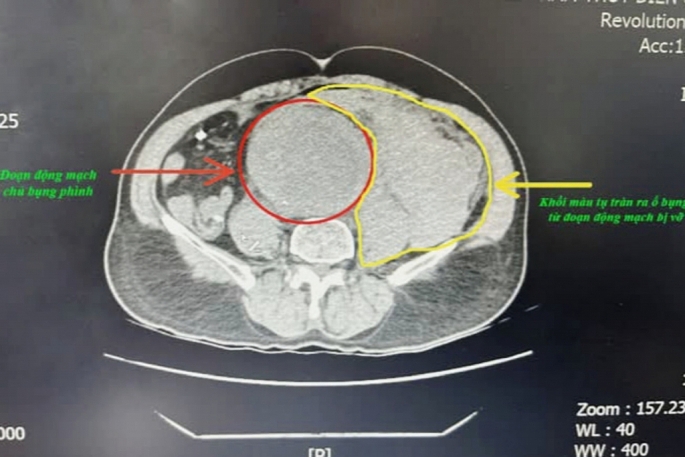

| Hình ảnh phim chụp đoạn phình động mạch và khối máu tụ do vỡ phình động mạch chủ bụng. Ảnh: BVCC |

Tại bệnh viện, bệnh nhân đau bụng dữ dội, da xanh nhợt, mạch không bắt được và huyết áp không thể đo được. Kết quả chụp CT Scanner cho thấy bệnh nhân bị phình động mạch chủ ngực đoạn dưới thận lan đến động mạch chậu hai bên, trong đó khối phình đã vỡ và gây tụ máu sau phúc mạc với số lượng lớn.

Trong quá trình phẫu thuật, các bác sĩ đã nhanh chóng kẹp động mạch chủ bụng trên và dưới túi phình để ngăn chặn tình trạng chảy máu tiếp tục vào ổ bụng. Kíp phẫu thuật ghi nhận ổ bụng của bệnh nhân chứa khoảng 2.000ml máu loãng lẫn máu cục, cùng với một vết rách lớn ở động mạch chủ vỡ vào sau phúc mạc. Bệnh nhân được thay thế đoạn động mạch chủ bụng bị phình bằng một đoạn động mạch nhân tạo.